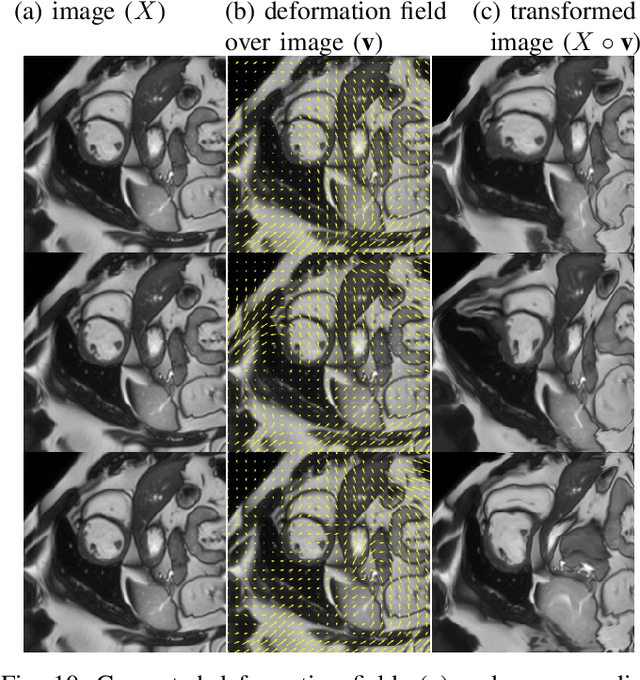

Abstract:Supervised deep learning methods for segmentation require large amounts of labelled training data, without which they are prone to overfitting, not generalizing well to unseen images. In practice, obtaining a large number of annotations from clinical experts is expensive and time-consuming. One way to address scarcity of annotated examples is data augmentation using random spatial and intensity transformations. Recently, it has been proposed to use generative models to synthesize realistic training examples, complementing the random augmentation. So far, these methods have yielded limited gains over the random augmentation. However, there is potential to improve the approach by (i) explicitly modeling deformation fields (non-affine spatial transformation) and intensity transformations and (ii) leveraging unlabelled data during the generative process. With this motivation, we propose a novel task-driven data augmentation method where to synthesize new training examples, a generative network explicitly models and applies deformation fields and additive intensity masks on existing labelled data, modeling shape and intensity variations, respectively. Crucially, the generative model is optimized to be conducive to the task, in this case segmentation, and constrained to match the distribution of images observed from labelled and unlabelled samples. Furthermore, explicit modeling of deformation fields allow synthesizing segmentation masks and images in exact correspondence by simply applying the generated transformation to an input image and the corresponding annotation. Our experiments on cardiac magnetic resonance images (MRI) showed that, for the task of segmentation in small training data scenarios, the proposed method substantially outperforms conventional augmentation techniques.